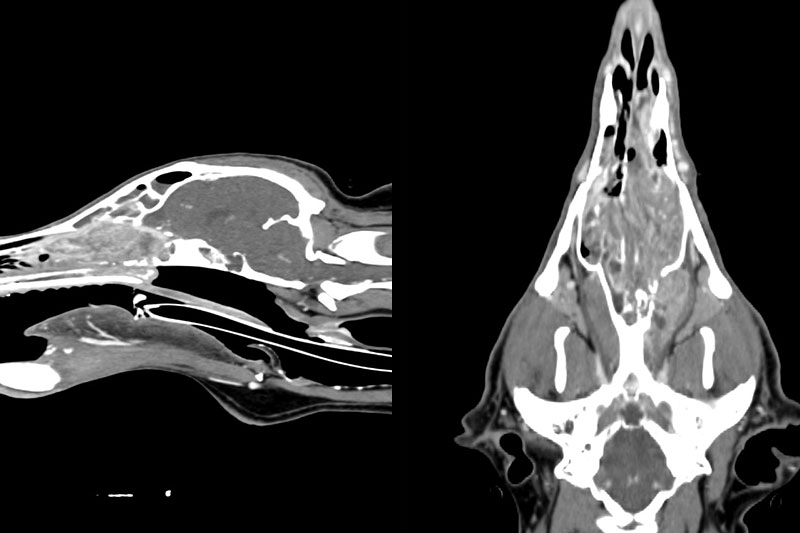

CT (Computed Tomography, 전산화 단층촬영) 검사는 X-ray를 이용해 반려동물의 몸을 여러 각도에서 촬영하고, 이를 컴퓨터로 합성하여 단면 이미지(슬라이스)를 만들어내는 정밀 진단 장비입니다.

사람 병원에서도 널리 사용하는 기술로, 뼈, 장기, 혈관, 종양 등 몸속 구조를 3차원(3D)으로 시각화할 수 있습니다.

| 두부(머리) | 뇌종양, 두개골 골절, 중이염, 치주염, 안와(눈) 질환 등 |